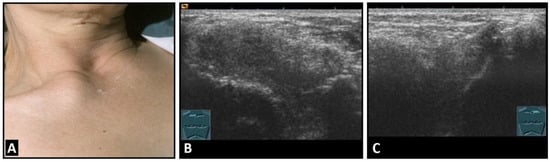

Figure 6.

A patient with painful swelling of the right sternoclavicular joint (A). B-mode US shows a hypoechoic swelling similar to that in Tietze syndrome (B) in comparison with the contralateral left joint (C).